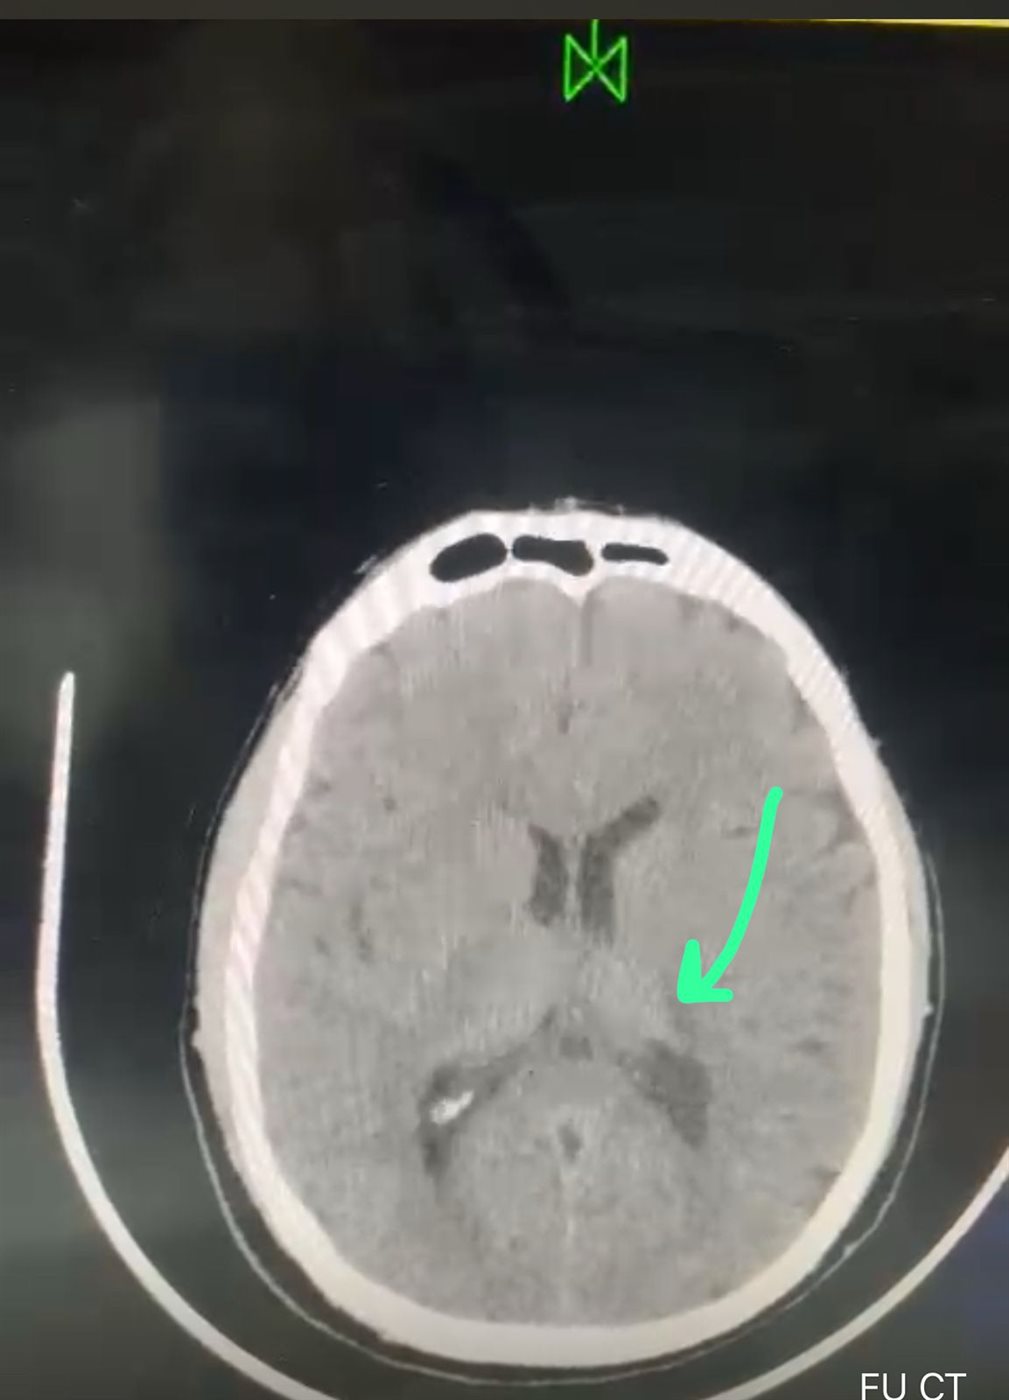

وأضاف مدكور أن طوارئ السنبلاوين كانت قد استقبلت مريضا يبلغ من العمر 54 عاما يعاني من ضعف وتنميل بالجانب الأيمن، وعقب إجراء والأشعة اللازمة تبين وجود جلطة احتشائية حادة نتيجة انسداد أحد الشرايين الرئيسية فى المخ. وعلى الفور تم حقنه بالعلاج ووضع الحالة تحت الملاحظة بوحدة إذابة الجلطة إلى أن استقرت وخرجت بعد تحسنها.

فيما أكد الدكتور أحمد البيلى وكيل المديرية للطب العلاجى على أهمية نشر الوعي عن وجود تلك الخدمة مجانًا بالمستشفى، وذلك لإنقاذ حياة المرضى وضرورة الانتباه للأعراض الأولية للجلطة الدماغية، والذهاب إلى المستشفى قبل مرور أربع ساعات علي الأعراض حيث أن نسبة النجاح حينها تتعدى ٧٠٪ مما ينعكس على المريض في تقليل حدوث مضاعفات ما بعد الجلطة.